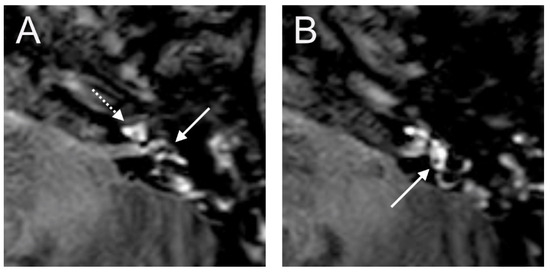

The VHIT showed a decreased VOR gain of the left anterior (0.00) and left posterior (0.33) canals, whereas the other VOR gain was preserved (>0.85). Moreover, a profound left canal paresis was observed with caloric tests. Intraoperatively, the round niche was wet, but CTP testing was negative. The contrast enhancement was seen in the left vestibulum and cochlea, and a SURI was observed here on the delayed postcontrast 3D-FLAIR sequences, suggesting vestibular endolymphatic hydrops, grade I (Figure 8). In the CT image, a dehiscence of the superior semicircular canal on the right side could be identified, but these could not be detected with contrast enhancement on the 4 h delayed 3D-FLAIR sequence. On in the T2W image was a hypointense signal intensity observed in the cochlea.

Figure 8. An 85-year-old female presented with sudden hearing loss on the left side with rotatory vertigo. The contrast enhancement was seen in the left cochlea ((A) dashed arrow) on the axial 4 h delayed 3D-FLAIR sequences. The inversion of the saccule ((A) arrow) to the utricle ((B) arrow) area ratio was observed.